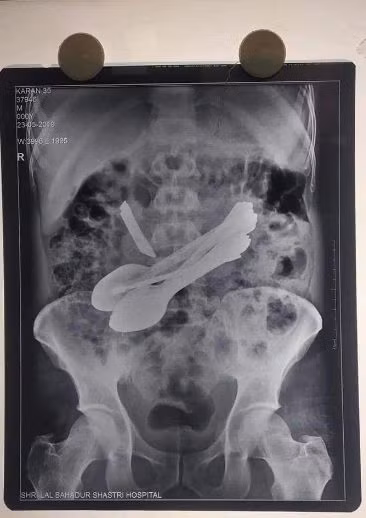

Ảnh chụp X-quang từ bụng của người đàn ông.

Các bác sĩ sau đó đã tiến hành phẫu thuật để loại bỏ những vật thể lạ trong bụng của Karan. Bác sĩ vô cùng choáng váng khi lấy ra được tổng cộng 14 vật thể trong dạ dày của người đàn ông này, bao gồm 8 chiếc thìa, 2 chiếc tuốc nơ vít, 2 bàn chải đánh răng, 1 con dao làm bếp và 1 chốt cửa.